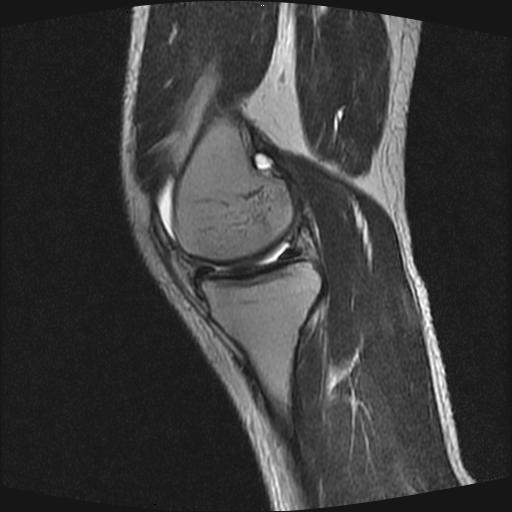

40岁男性,右膝关节外伤,x光平片示,髁间隆突撕脱骨折。

1、前交叉韧带撕裂;

2、外侧半月板后角撕裂;

3、关节腔积液。

前交叉韧带撕裂,关节腔积液.

半月板1-2级损伤   前交叉韧带撕裂伤   关节腔少量积液  诸骨未见新鲜外伤性改变

髁间隆突撕脱骨折;内侧副韧带损伤。

内侧副韧带撕裂及关节腔积液是肯定的,但是前交叉撕裂确定吗?会不会有容积效应的因素,因为前一张前交叉显示清楚,连续性良好,且较光滑。请问楼主有关节镜支持吗?我们医院也经常有这样的患者,但苦于没有关节镜,而无法对照、证实(除非完全断裂),出现了不同的诊断结果只能毫无意义的争论。

1、前交叉韧、内侧副韧带撕裂;

3、关节腔积液。4、髁间脊撕脱骨折。

除了关节积液外并无韧带撕裂,acl胫侧附着点有2束,正常情况下脂肪信号。此病例应加做压脂像以便观察是否有骨损伤。